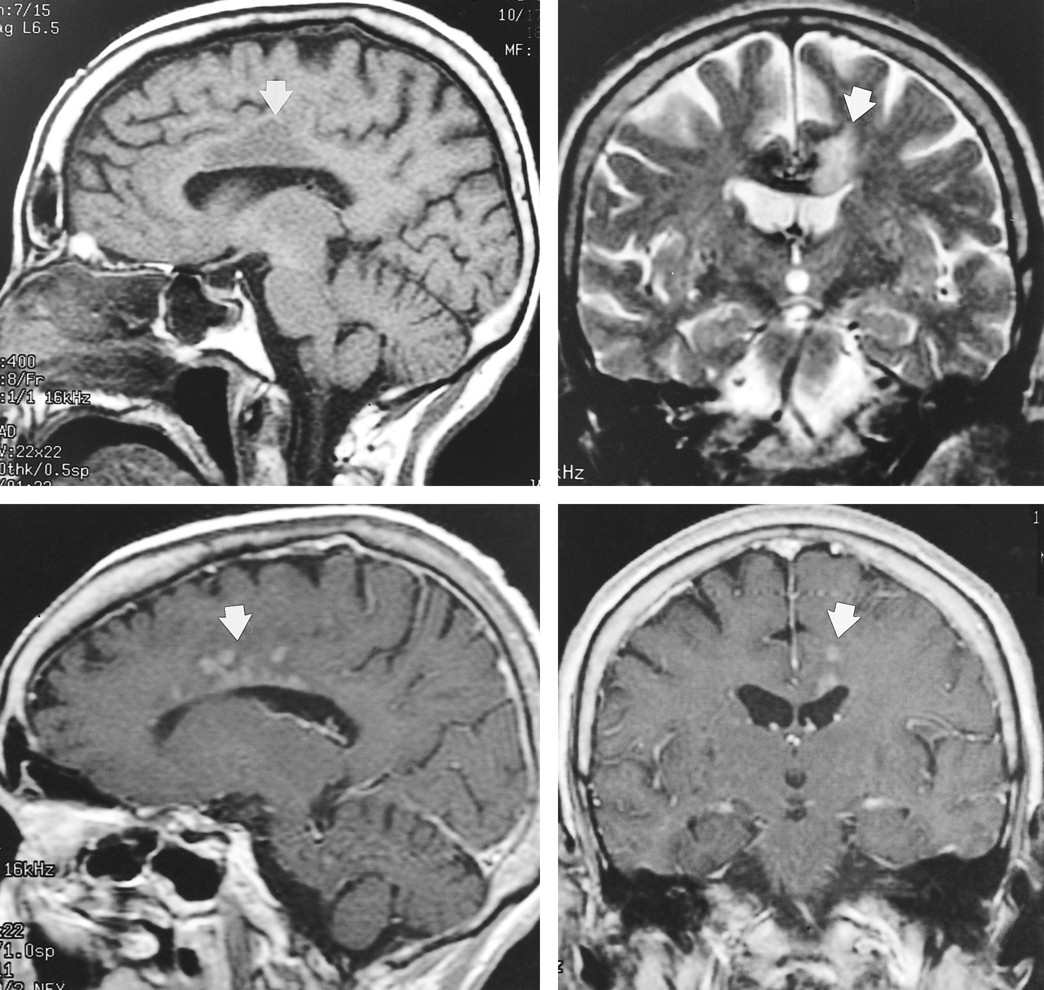

A 79-year-old woman, with past medical history significant for hypertension, presented with a 3-week history of intermittent right-leg numbness and weakness. CT and MR imaging (Figures 4A and 4B) performed 4 days after admission showed low attenuation and abnormal signal intensity, respectively, within the left side of the corpus callosum and adjacent white matter, with mass effect on the left frontal horn. No other abnormality was noted. The diagnosis of tumor was considered, given the history of intermittent symptoms that continued during the next 4 weeks. Ill-defined enhancement was noted on a follow-up contrast-enhanced MR examination (Fig 4C and D), obtained 5 weeks post admission, further supporting the consideration of a neoplasm. A subsequent MR examination revealed resolution of the enhancement.

Case 4. Sagittal non-contrast T1- (A) (400/10/1) and coronal T2-weighted (B) (2500/105/1) images show abnormal signal within the body of the corpus callosum and adjacent white matter (arrow) on the left side. Sagittal (C) (400/8/2) and coronal (D) (450/20/1) postcontrast T1-weighted images from a subsequent MR examination show abnormal enhancement (arrow) within the corpus callosum and adjacent white matter